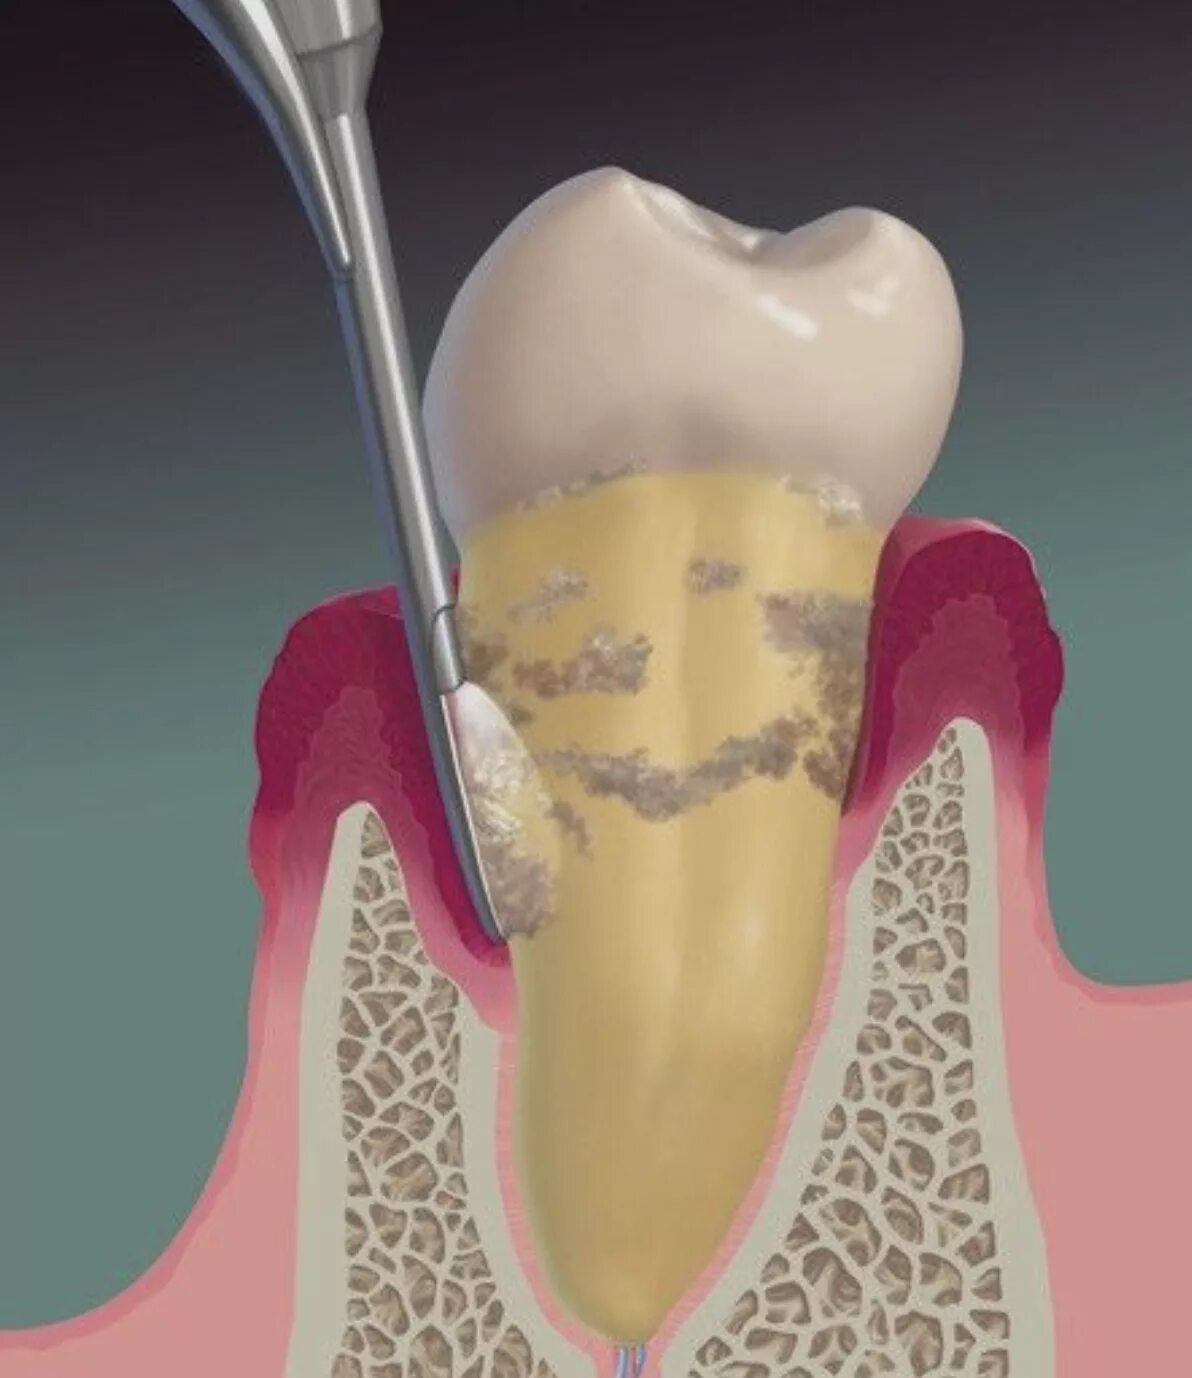

Зубной карман